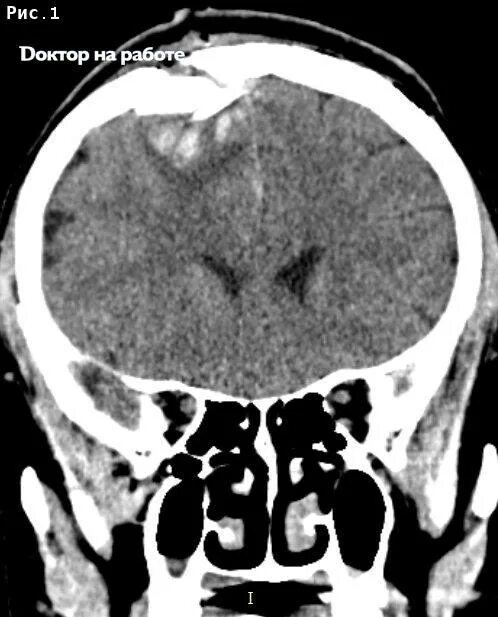

Форум после кт